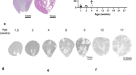

Cul3 disruption causes sustained proximal tubule injury and inflammation

To determine the time-course of kidney injury, we analyzed mice 2, 4 and 8 weeks after initiating Cul3 deletion (Fig. 3a,b). PAS staining showed progressive acute tubule injury characterized mainly by brush border loss, epithelial flattening, tubule dilation and intratubular debris (Fig. 3c,d). H&E staining showed similar kidney morphology (see Supplementary Fig. S3a). At week 8, there was a significant loss of LTA+ brush border, suggesting continued PT injury (Fig. 3e). This was supported by increased abundances of KIM-1, Neutrophil gelatinase-associated lipocalin (NGAL), cleaved caspase-3, γ-H2AX and Ki-67 over the time course (Fig. 3f–i,l–o; see Supplementary Fig. S3b–e). Infiltrating cells were positive for the T-cell marker CD3 (Fig. 3j,p) or macrophage marker F4/80 (Fig. 3k,q; see Supplementary Fig. S3f), but other infiltrating cell types may also have been present.

Cul3 disruption causes sustained proximal tubule injury and inflammation. (a,b) To assess the progression of CUL3-mediated renal injury, Cul3 disruption was induced by doxycycline administration, and kidney-specific Cullin 3 knockout (KS-Cul3−/−) mice were evaluated after 2, 4 and 8 weeks. (c,d) Periodic acid-Schiff staining revealed progressive tubule injury characterized by cellular infiltration (arrowheads), very discrete subapical vacuolization (double-headed arrow) and dilated tubules with brush border loss, epithelial flattening and intratubular debris (arrows) upon Cul3 disruption. (e) LTL- immunolabeling of kidney sections after 8 weeks of Cul3 deletion indicated loss of brush border, i.e. a proximal tubule injury, in Cortex (C) and outer stripe of outer medulla (OSOM). (f–q) Cul3 deletion caused progressive tubule injury and inflammation with positive staining for KIM-1 (f,l) and neutrophil gelatinase-associated lipocalin (NGAL) (g,m), cleaved capsase-3+ apoptosis (h,n), γ-H2AX+ DNA damage (i,o), CD3+ T-cell infiltration (j, p) and F4/80+ macrophage activation (k,q). Scale bars = 100 μm; except in (e) = 500 μm). n = 3. Mean values are shown ± SEM. Asterisks show significant differences between control and each KS-Cul3−/− mice group. *P ≤ 0.05, **P ≤ 0.01, ***P ≤ 0.001, ****P ≤ 0.0001; ordinary one-way ANOVA with Dunnett’s multiple comparisons test. Abbreviations: n.s., not significant; n.d., not detectable. Coomassie-stained gels used for Western blot normalization can be found in Supplementary Fig. S4. Western blots were cropped for clarity; uncropped images can be found in Supplementary Fig. S7.